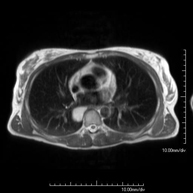

Prova diagnòstica no invasiva que consisteix en l'obtenció d'imatges d'alta definició anatòmica del mediastí mitjançant l'ús d'un camp electromagnètic i ones de ràdio (amb un emissor i un receptor). No utilitza radiació ionitzant. El mediastí és la part central de la caixa toràcica que inclou el tim, els grans vasos (aorta toràcica, vena cava inferior i superior, etc.), el cor, la tràquea i els bronquis principals, els ganglis limfàtics mediastínics i hilars, l'esòfag, etc. Està especialment indicada en lesions mediastíniques per diferenciar si són quístiques o sòlides, en el diagnòstic diferencial de les lesions del mediastí anterior, etc. De vegades s'ha d'emprar contrast paramagnètic (Gadolini) per completar l'estudi. - RM Tòrax

Prova diagnòstica no invasiva que consisteix en l'obtenció d'imatges d'alta definició anatòmica del tòrax mitjançant l'ús d'un camp electromagnètic i ones de ràdio (amb un emissor i un receptor). No utilitza radiació ionitzant. Està indicada en aquelles lesions pulmonars en les quals s'ha de descartar si hi ha infiltració del mediastí o de la paret toràcica, per diferenciar si una lesió toràcica és sòlida o quística, etc. En alguns casos caldrà emprar contrast paramagnètic (Gadolini) per completar l'estudi. - RM de Paret Toràcica